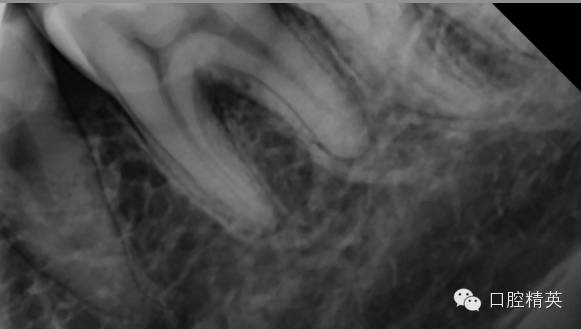

病例是36一次性根充,患者女性,68岁,半年前因冷热不适36外院有充填史,但无好转,近日加重,夜间痛自发痛,疼痛放散至头面部,查:36冷测(++)扣痛阳性,不松,牙髓电活力测试17,龈正常,诊断:不可逆性牙髓炎

这是个严重钙化的牙齿

严重钙化,打开根本找不到根管口![今天的病例,36一次性根充]()